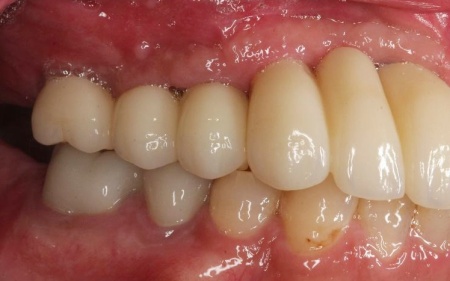

50代男性 バランスが崩れた噛み合わせをインプラント治療と被せ物治療で改善した症例

インプラントが骨にしっかりとなじんだことを確認したら、白くて強度の高い人工歯「ジルコニアクラウン」を装着しました。

左下奥歯1本、右下奥歯2本に装着されていた古い被せ物はすべて外し、ジルコニアクラウンと交換しました。

最後に、見た目や噛み合わせに問題がないかを確認し、治療を終了しています。